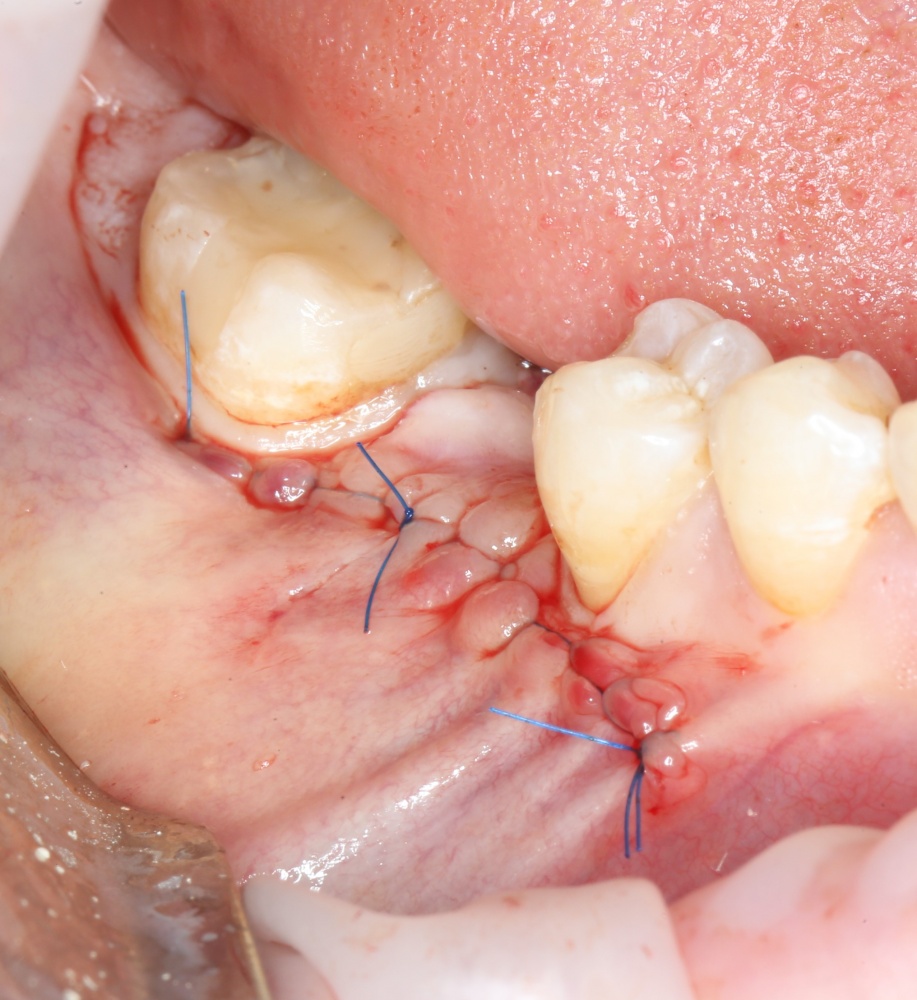

Наложение швов.

Если на этапе разреза и формирования раны всё сделано правильно, то наложение швов не вызывает особых трудностей. Периостотомия или послабляющие разрезы на периосте не требуются (ни практически никогда не требуются). А сами швы получаются аккуратными и герметичными:

Обрати внимание, что все шовные лигатуры находятся в пределах кератинизированной десны. Это позволяет избежать деформации тканей и лишних рубцов. В наиболее уязвимых местах (около зубов) шовные лигатуры лучше продублировать.

Если бы мне пришлось делать это сейчас, то я бы использовал непрерывный «матрацный» шов. Он удобнее, быстрее в наложении и комфортнее для пациента. Минус — если распускается, то распускается весь. К тому же, его очень неудобно снимать.

Несмотря на то, что уже тогда мы широко использовали непрерывные швы в подобных случаях, здесь я, во-первых, зассал (может распуститься), во-вторых, снятие швов предполагалось в поликлинике по месту жительства пациентки, и мне не хотелось, чтобы там при снятии швов начудили. Как выяснится позже — зря беспокоился.

Неизменно одно — в таких операциях мы использовали и до сих пор используем нерезорбируемые монофиламентные шовные материалы, поскольку они наиболее гигиеничные. Чтобы острые концы нитей не беспокоили пациента, их можно оплавить нагретой гладилкой или гуттаперчевым плаггером.